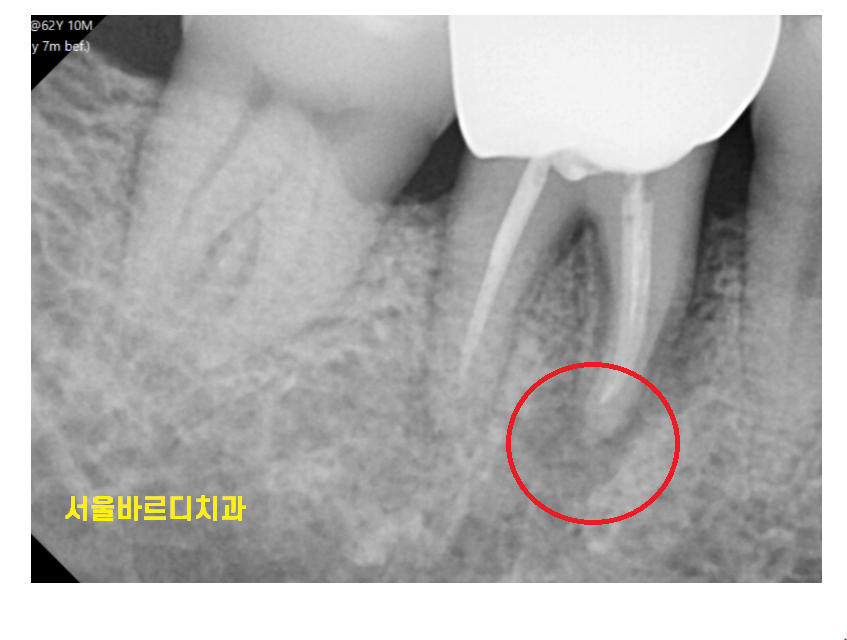

부러진 부위는

까맣게 변했을정도로 상태가 안좋았습니다.

외관상의 문제보다

뿌러지고 방치 되면서

치아 주변 뼈가 녹은게 관찰됩니다.

통증이 있는 상태라

해결을 위해서는 치아를 뽑아야 했는데요.